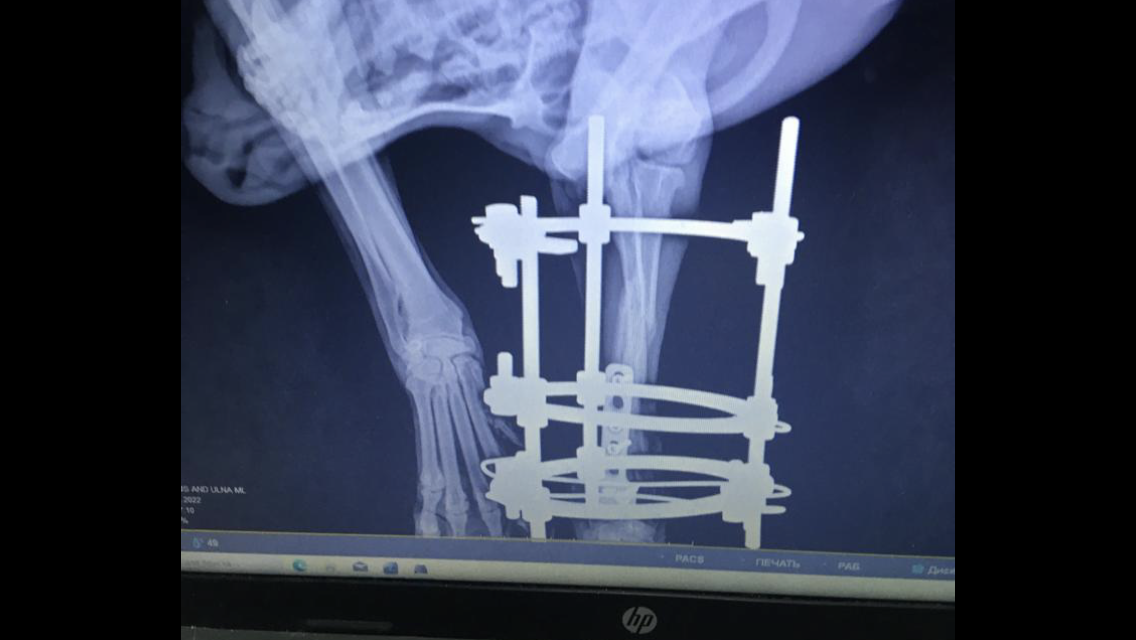

Карату поехали снимать конструкцию

Перенёс операцию, поставили ему конструкцию Елизарова

Осмотр и рентген, как Вы видите рентген показал, что кости срастаются очень медленно, была тяжёлая травма и сложная операция, конструкцию снимать рано...